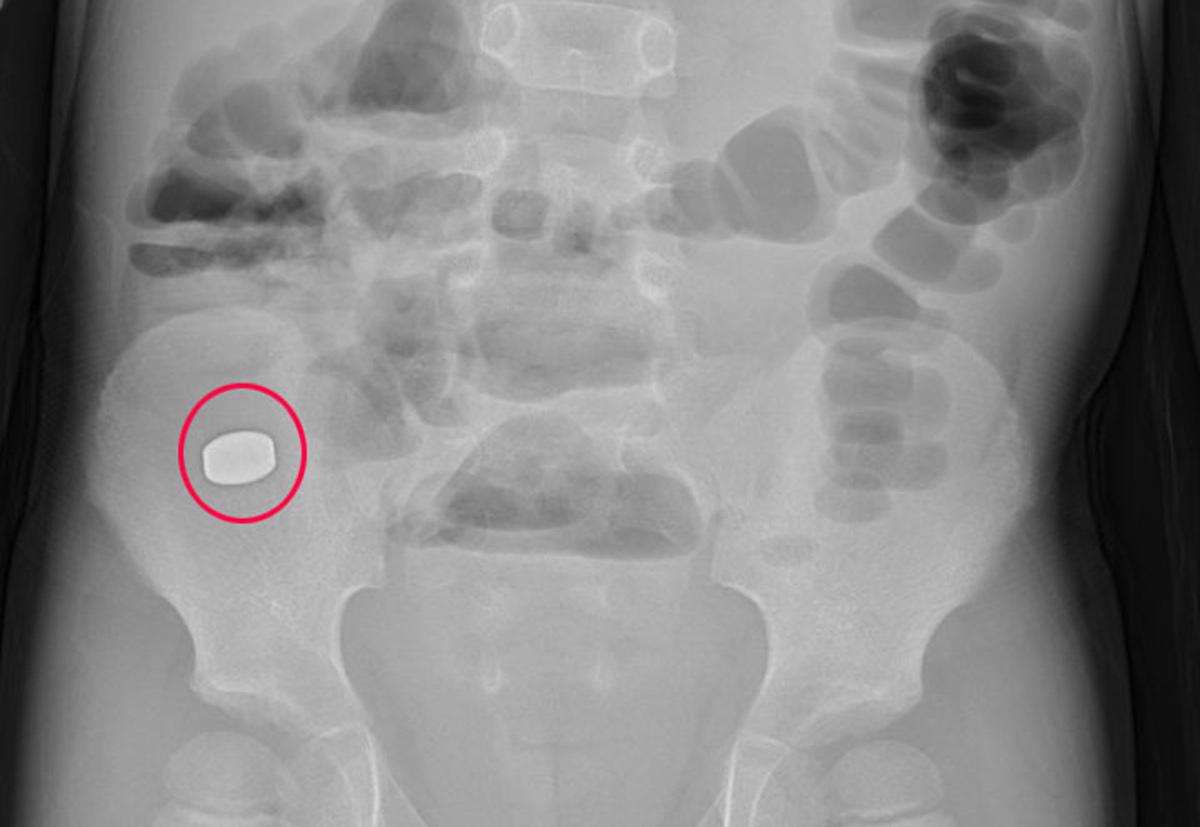

Bé 5 tuổi ở Quảng Ninh nuốt phải cục nam châm trong đồ chơi

Diệu Hoàng |

Tại Bệnh viện Việt Nam – Thụy Điển Uông Bí (Quảng Ninh), kết quả chụp X-quang, xác định cục nam châm trong đường tiêu hóa vị trí tại hố chậu phải của bệnh nhi.